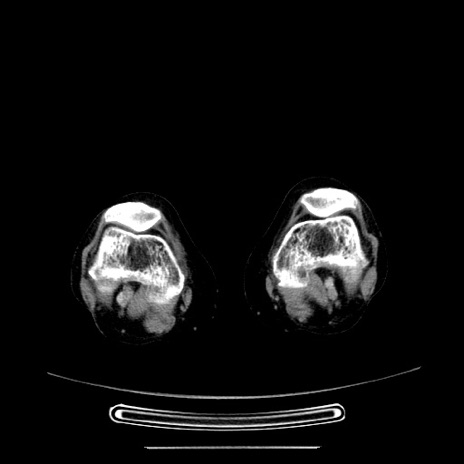

症例5(横断像)

【症例】70歳代女性

【主訴】お腹が張る

【現病歴】1週間くらい前から腹部膨満の自覚あり。昨日夜から増悪したため、本日救急外来受診。

【身体所見】意識清明、BT 36.5℃、BP 165/106mmHg、HR 80bpm、SpO2 98%、腹部:膨満、軟、自発痛・圧痛なし、触診にて不快感あり、腸蠕動音:減弱

【データ】WBC 12600、CRP 1.04